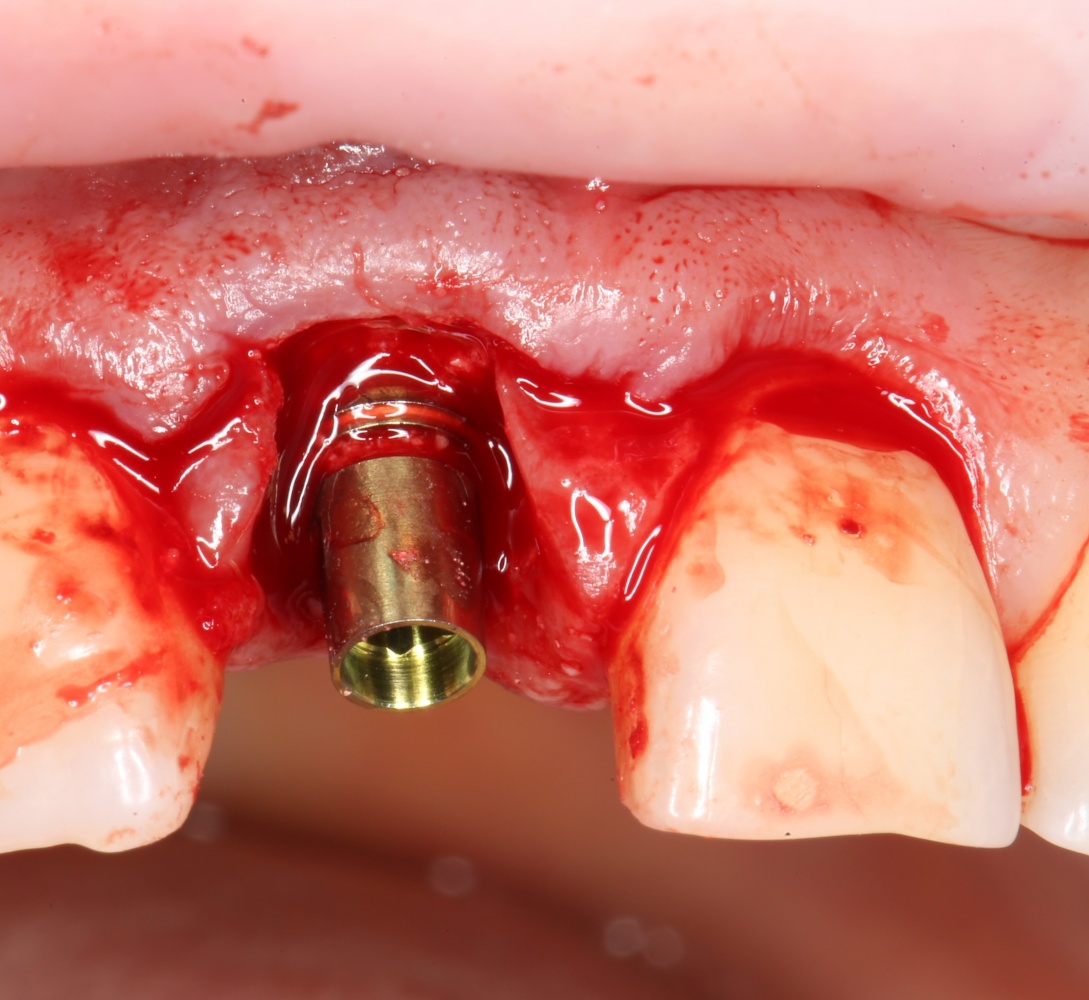

Все начинается с удаления зуба:

Обратите внимание на состояние вестибулярной стенки лунки. В проекции верхушек корней вы можете увидеть костный дефект, вызванный длительным воспалительным процессом (собственно, почему этот зуб пришлось удалять). В этом случае, вестибулярная стенка лунки неизбежно лизируется после удаления зуба, а это приведет не только к проблемам в эстетике, но и осложнит последующий уход за протетической конструкцией. Поэтому в данном случае мы должны продумать, в том числе, аугментацию лунки. И порядок действий здесь несколько иной, нежели в предыдущем случае.

Устанавливается имплантат Astratech (Dentsply Implants):

Для аугментации также используем Bio-Oss Collagen 100 mg, нарезаем его по размеру с помощью скальпеля и позиционируем в лунках щечных корней:

На имплантат ставим формирователь, ушиваем лунку. Напомню, что любой биоматериал должен быть герметично запечатан в ране (фактор успеха III). В противном случае, от него больше вреда, чем пользы:

Совсем уж стягивать края раны не нужно (если бы мы использовали обычный Bio-Oss, то это было бы необходимо). Отличие Bio-Oss Collagen еще и в том, что он не размывается при кровотечении.